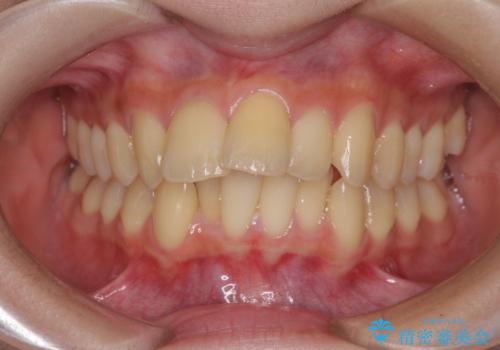

掃除しにくい前歯と閉じにくい口元 目立たないワイヤー装置での抜歯矯正